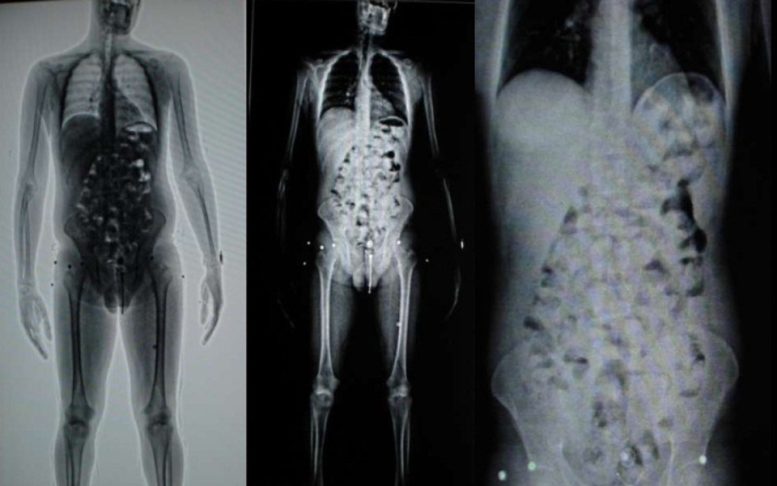

Ao todo, 18 pessoas foram identificadas transportando cocaína na modalidade conhecida como “engolidos”, em que os envolvidos ingerem cápsulas da droga para tentar ocultar o crime. Um dos suspeitos não conseguiu ingerir todo o entorpecente e parte da cocaína acabou sendo escondida em frascos de shampoo. Os outros 17 transportavam cerca de um quilo da droga cada um, ingerida em cápsulas.